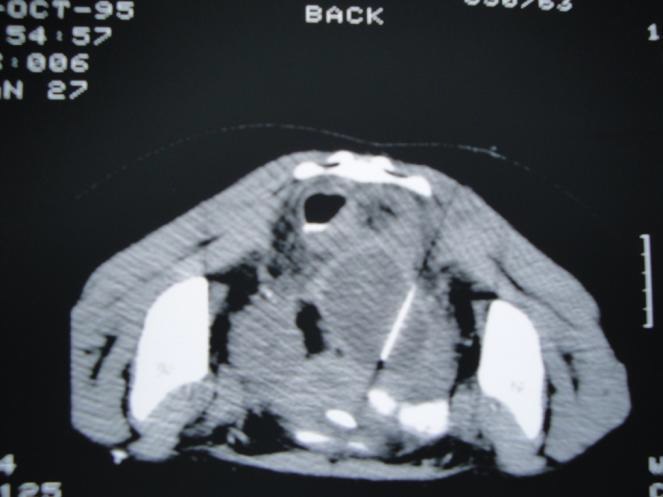

经直肠(Transrectal)

同直肠相临的脓肿可能可以经直肠引流。经直肠入路进行外科手术引流的方法已经比较成熟,但一般需要全身麻醉并且要求经直肠能够触到脓肿。在影像引导下进行引流就能克服这些问题,并且有多种手段可以进行这种引导。透视引导的引流就是在肛镜或一个改良的enema tip下插入针头。也可以采用CT引导。

最早描述的超声引导方法是经腹的,最近已经出现了经直肠超声并且可以同透视联合应用。 US-Guided Transrectal Drainage:Seldinger technique

在直肠前部或后部的脓肿都可以经直肠引流。不要求可以触到脓肿。使病人处于左侧卧位,在影像监控下将针头插入直肠,针头原来是回缩在它的鞘里的。可以用带着手套的手指,塑料管,或活检导轨贴附在经直肠探针上,根据采用的影像学方法帮助针头的定向。整个过程几乎是无痛的,并且可以有相当好的耐受。通常不必要进行局麻和静脉用镇静剂。在使用锁定导管(locking catheter)时,不需要固定皮肤,但病人下地活动时就必须固定皮肤了。

这项技术的一个缺点在于导管的早期脱出,在排便时就可能发生。这样脓肿就可能重新形成,但通常可以通过再次经直肠引流治疗。Lomas等人认为使用大管径的导管将会在导管脱出的情况下仍然保持通道开放,但这一点还没有得到证明。总体的成功率可以同经腹引流相比较。

没有B超引导也可以考虑在透视引导下直接穿刺